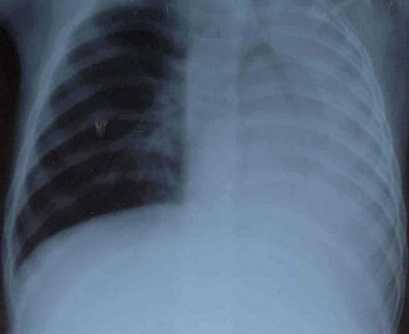

Диагноз подтверждается рентгенологически. Рассеянный ателектаз легких у новорожденных на рентгеновском снимке представлен множественными участками затемнения небольших размеров. Характерно преимущественно паравертебральное расположение безвоздушных областей. Сегментарный ателектаз легких у новорожденных выглядит, как обширный участок затемнения. При высокой разрешающей способности аппаратуры можно заметить сморщенный участок легочной ткани возле корня легкого. Часто отмечается смещение сердца в пораженную сторону и более высокое стояние диафрагмы со стороны ателектаза. Для подтверждения диагноза, особенно при подозрении на обструкцию дыхательных путей, показана бронхоскопия.

Основу инструментальной диагностики ателектаза легкого составляют рентгенологические исследования, прежде всего, рентгенография легких в прямой и боковой проекциях. Для рентгенологической картины ателектаза характерно гомогенное затенение соответствующего легочного поля, смещение средостения в сторону ателектаза (при коллапсе легкого - в здоровую сторону), высокое положение купола диафрагмы на пораженной стороне, повышенная воздушность противоположного легкого. При рентгеноскопии легких на вдохе органы средостения смещаются в сторону спавшегося легкого, на выдохе и при кашле - в сторону здорового легкого. В сомнительных случаях данные рентгенографии уточняются с помощью КТ легких.

При проведении рентгенологического исследования на рентгенограммах определяется тень, имеющая четкие вогнутые границы. При проведении рентгеноскопии у пациентов с ателектазом легкого можно выявить симптом Якобсона-Гельцнехта (толчкообразные смещения тени средостения, направленные в сторону поражения).

Проводится диагностика при помощи рентгенологического исследования в разных проекциях. На снимки видно затемнение травмированного участка легкого, диафрагма занимает повышенное положение по отношению к пораженной стороне. Часто снимки не дают поставить точный диагноз, и тогда диагностика проходит при помощи другого метода — компьютерная томография легких.